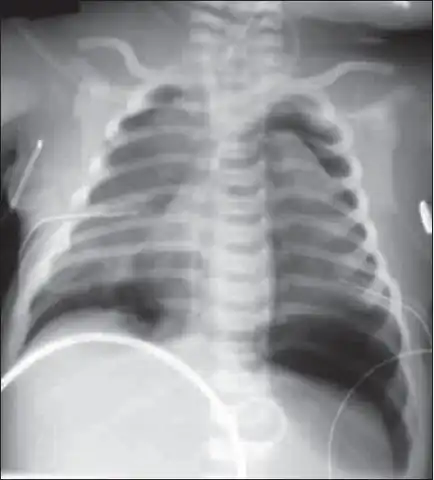

X-ray showing lung damage in response to meconium in a newborn.

In about 10% of cases babies pass meconium before delivery.[1] Risk factors include fetal distress, postterm pregnancy, and emergency cesarean section.[3] If this is subsequently breathed into the lungs it may result in inflammation of the lungs and blockage of airways.[1] Diagnosis is based on symptoms and a chest X-ray.[1]